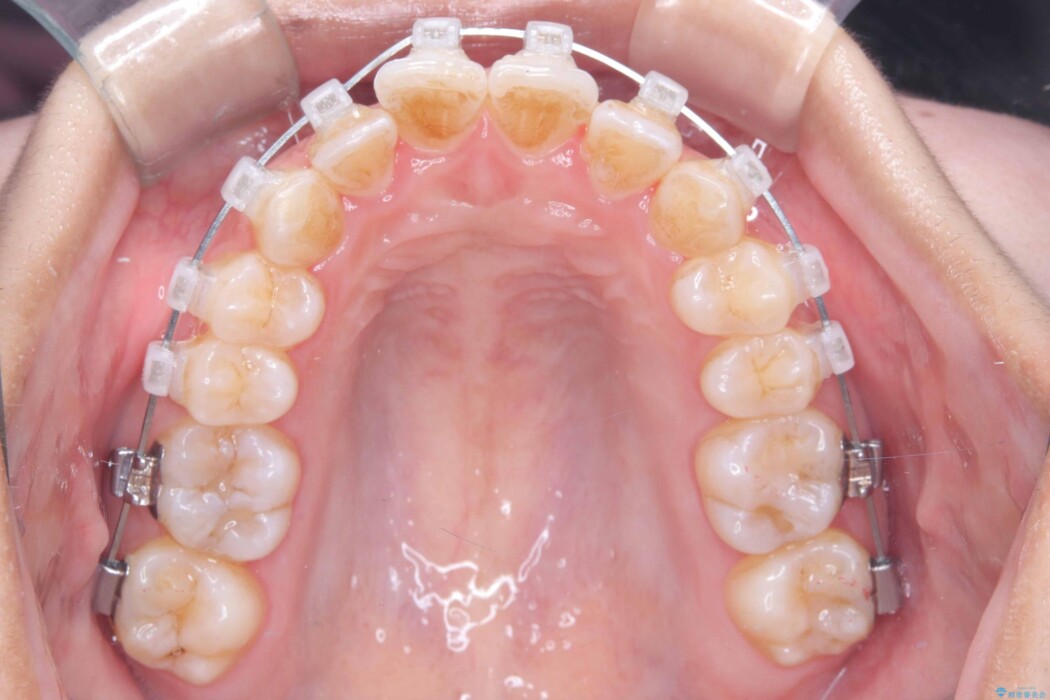

歯のガタつきが気になるとご来院された患者様です。

矯正検査の結果、非抜歯にてワイヤー矯正を行うこととしました。

ガタつきのほかに反対咬合も認められたため、見た目だけでなく嚙み合わせも同時に改善していきます。